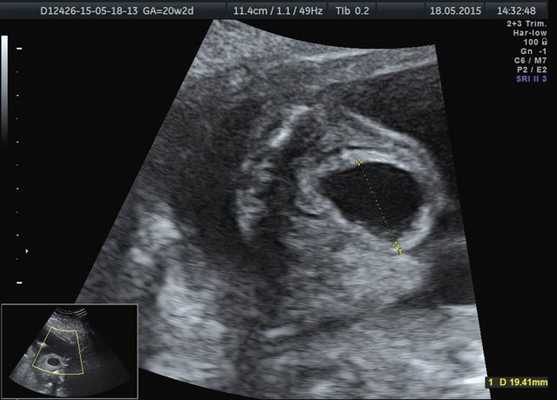

При ультразвуковом исследовании обнаружен один живой плод. Гестационный срок составил 22,1 нед. Фетометрические показатели соответствовали данному сроку. Патологических изменений плаценты и околоплодных вод не было выявлено.

Лоханка правой почки была расширена до 13 мм, паренхима истончена и гиперэхогенна, кортикомедуллярная дифференцировка отсутствовала. При ЦДК кровоток в паренхиме не визуализировался. Вокруг правой почки по всему ее периметру определялось анэхогенное образование размером 56×20×26 мм (рис. 1, 2). Мочеточники с обеих сторон не визуализировались. Изменения левой почки отсутствовали. Мочевой пузырь был удовлетворительного наполнения и опорожнения. Оба надпочечника визуализировались.

Рис. 1. Образование вокруг правой почки плода.